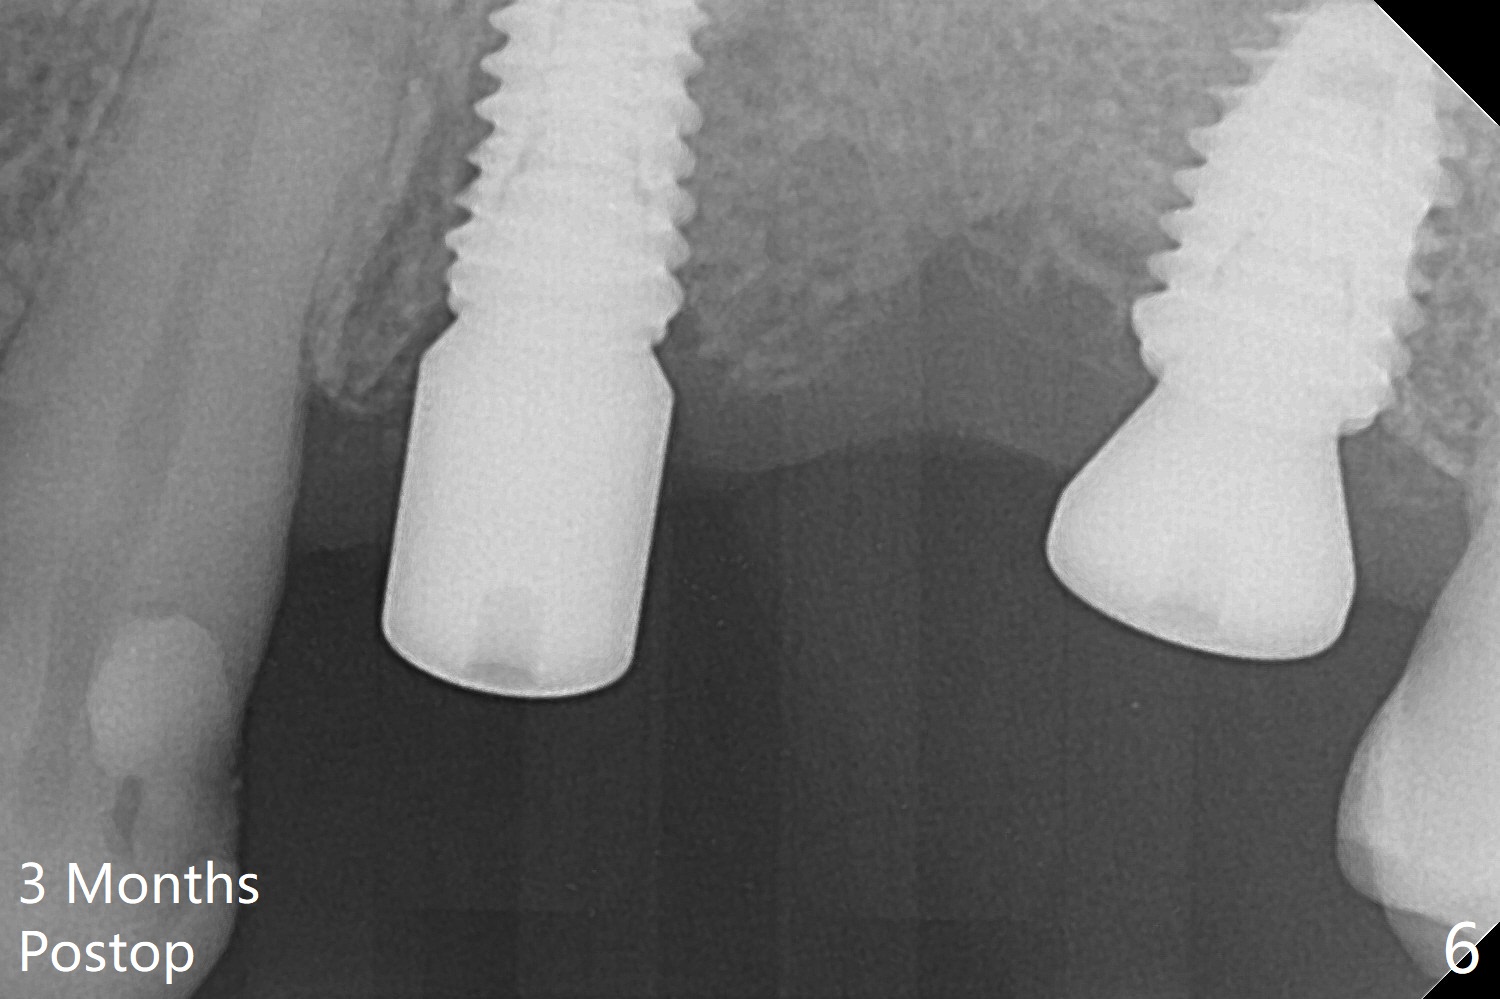

The implants at #12 and 14 are placed 1 month later (Fig.4). The 4 implants have impression (Fig.5,6) and cementation (Fig.7-9) at the same time. Although the upper FPD is able to be removed after cementation in the mouth (Fig.7), the abutment screw cannot be tightened >20 Ncm (Fig.8). The tooth #15 is tender early after crown/FPD cementation and needs occlusal adjustment twice. The crown of #18 dislodges eight months post cementation (Fig.11 taken after recementation). There is no bone loss at #13 and 15 (Fig.10), while the bone density increases around the implants at #18 and 19 eight months post cementation (Fig.11). The abutment screw at #18 become loose 1.5 years post cementation; after proximal surface trimming twice (<), the abutment remains incompletely seated (Fig.12,13). With suspicion of soft tissue block (Fig.13 *), a small abutment with longer cuff is completely seated (Fig.14).